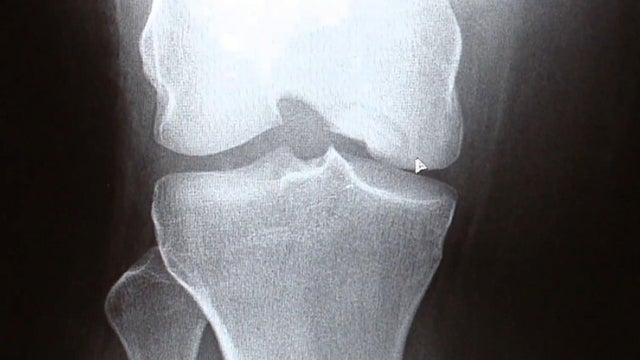

By attaching small microphones to knees, doctors can detect high frequency sounds in the joints as people sit and stand.